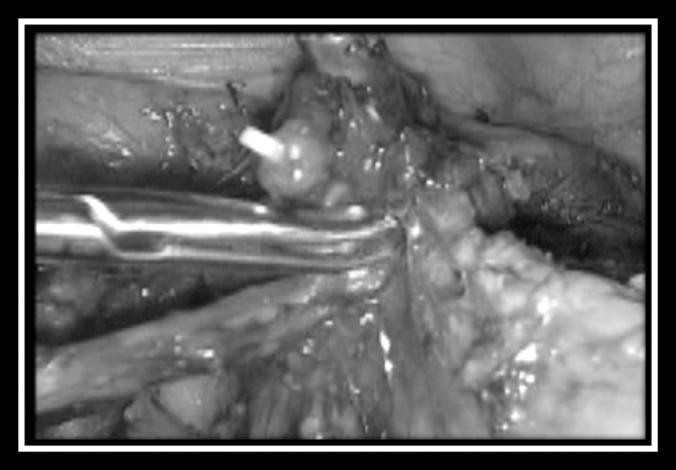

We analyzed 4 patients who underwent laparoscopic radical trachelectomy for early-stage cervical cancer between December 2011 and May 2013.

Four patients were included in this study. Total laparoscopic radical trachelectomy was performed in all cases. The mean age was 26 years (range, 19-32 years), the mean body mass index was 21 (range, 18-23), and the mean length of hospital stay was 33 hours (range, 24-36 hours). The mean operative time was 225 minutes (range, 210-240 minutes), and no complications were reported. During the postoperative period, only 1 patient presented with left vulvar edema, which resolved spontaneously. The pelvic and parametrial lymph nodes, as well as the vaginal cuff and cervical resection margins, were negative for malignancy in all cases. On average, 18 pelvic lymph nodes (range, 15-20) were removed. The tumor stage was IB in all 4 patients, and the mean tumor size was 17 mm (range, 12-31 mm). No patient required conversion to laparotomy.